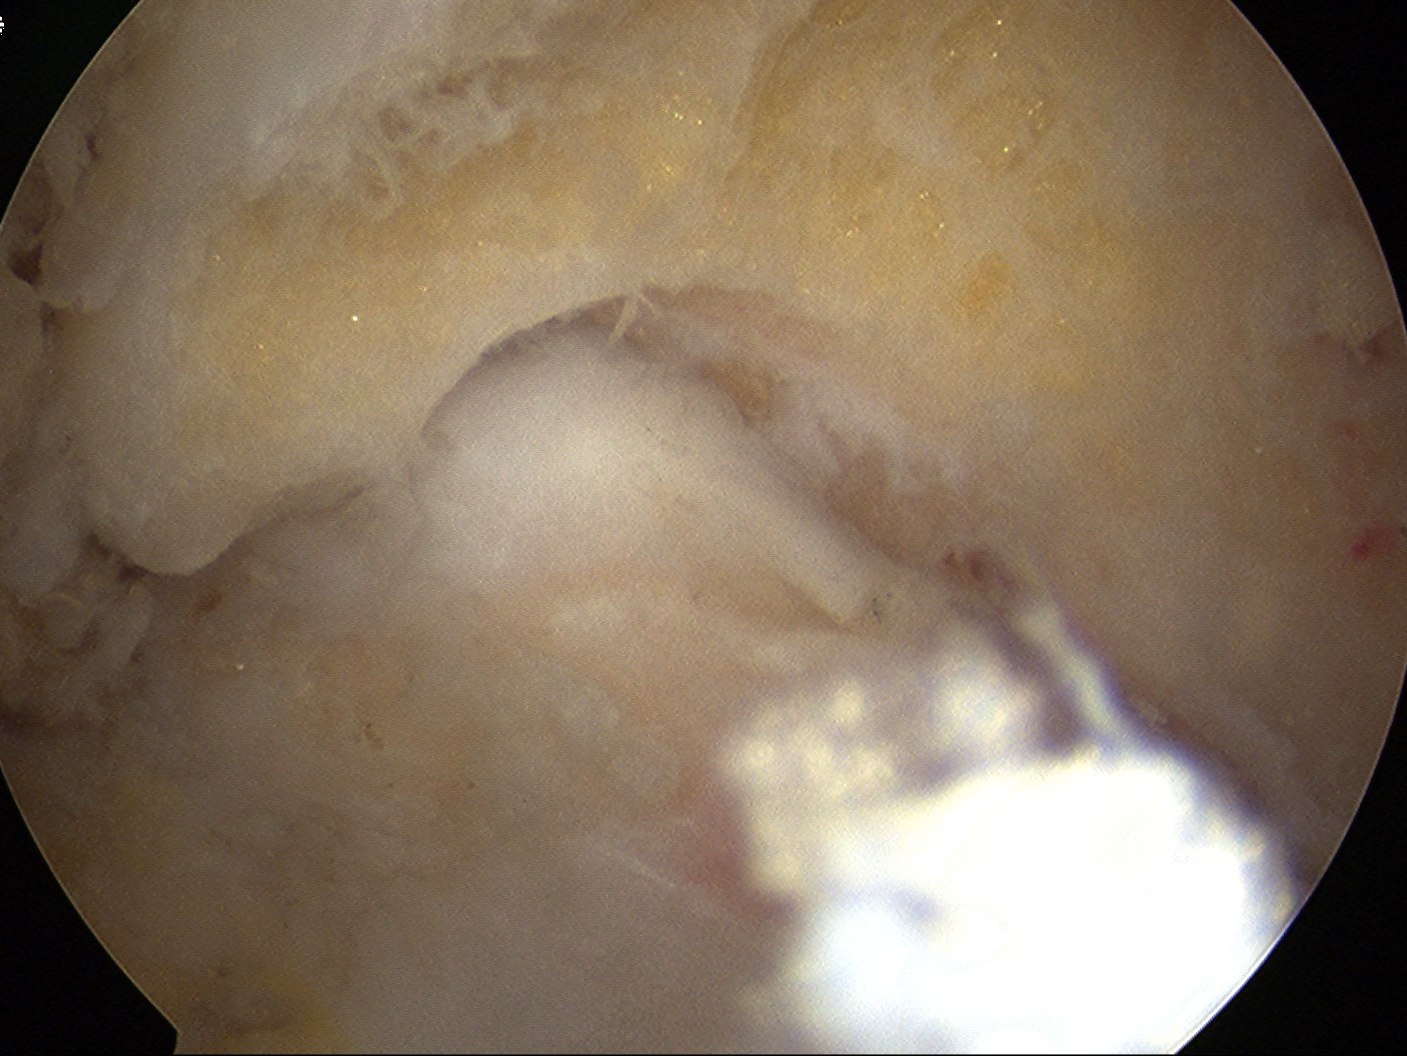

Loose body in elbow joint

Before and after resection of olecranon osteophyte

Post debridement of the tip of the olecranon, in the flexed and extended elbow position

Elbow extension pre and post arthroscopic debridement